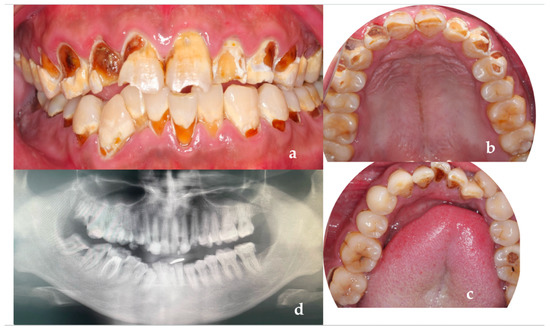

A 26-year-old male patient came to our clinic because of spontaneous pain in his right posterior tooth for one week. The patient had no systemic disease, and the family history showed no abnormalities. He described his job as a waiter with no exposure to acid substances. However, he loves to drink Coca-Cola and drinks more than 1 L of Coca-Cola every day; he also loves snacks and brushes his teeth less than once a day. These are the main causes of his dental caries. Dental examination found that the patient had poor dental hygiene with I-II° calculus supragingival and subgingival. All his teeth had extensive caries on the cervical region of the buccal and labial surfaces. The caries of teeth #14–24 even invades the tooth cusps. No lesions were found in the palatal and lingual surface. The pulpal surfaces of erosive lesions contained brown-colored, leathery, carious dentin. None of the pulp cavities were involved and the teeth remained asymptomatic on percussion, palpation and cold testing, except for tooth #46. The patient’s toothache came from tooth #46. There were two visible holes in teeth 46 buccal and occlusal surface, the perforation could be detected in the buccal surface, and the probing pain was obvious. There was no pain on percussion but severe pain on cold testing and heat testing (Figure 2a–d).

Figure 2.

(a) The photograph of the patient at first visit; (b) Upper teeth; (c) Lower teeth; (d) Panoramic X-ray of the patient (after the root canal therapy of teeth 46).